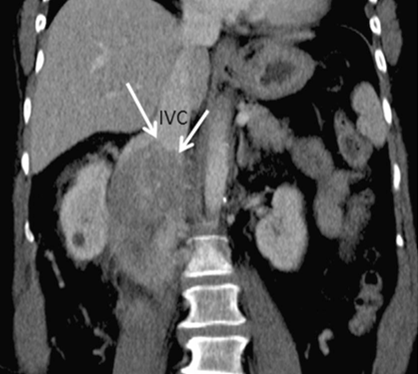

增强CT冠状位成像,箭头指示:下腔静脉(IVC)被嵌在一个呈不均匀强化的软组织肿块内,器官(下腔静脉)嵌入器官征阳性,提示该肿块起源于下腔静脉,最终被证实为原发性平滑肌肉瘤